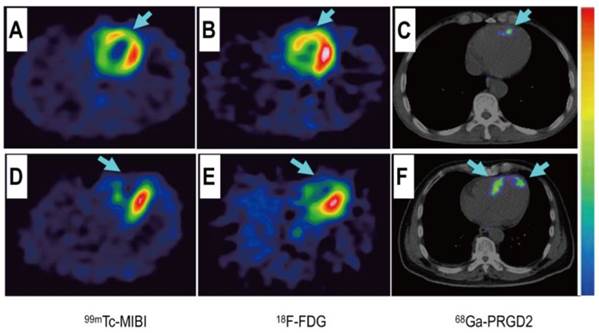

Figure 5

2D projection images of [18F]Alfatide II (A) and [18F]FDG PET (B) of a patient with metastatic adenocarcinoma of unknown primary site. [18F]Alfatide II PET demonstrated intense local accumulation of radioactivity in the bone metastatic lesions located in thoracic vertebras, sacrum and right scapula, and right clavicle with good background contrast, whereas [18F]FDG PET only showed moderate uptake in some thoracic vertebras and sacral lesions. The transaxial CT (C), [18F]Alfatide II PET (D), and [18F]FDG PET(E) were presented to focus on the lesions at sacrum. There is also bone metastasis with abnormal [18F]Alfatide II uptake (G) but not visible by transaxial CT (F) or [18F]FDG PET(H). Reproduced with permission from reference [66].

[18F]FPPRGD2 was the first dimeric RGD peptide tracer applied in the clinic for PET imaging [64]. In a clinical study with 8 breast cancer participants [65], primary and metastatic lesions showed [18F]FPPRGD2 uptake with SUVs of 2.4-9.4 (mean, 5.6 ± 2.8) and 2.5-9.7 (mean, 5.0 ± 2.3) at 60 min p.i. (Figure 4A). No significant difference in SUVs was found between [18F]FPPRGD2 and [18F]FDG PET, for both primary lesions and metastases. Similar results were also reported in a recent study which compared [18F]FPPRGD2 with [18F]FDG PET in 35 patients [38]. The average tumor SUVs from [18F]FPPRGD2 PET is higher than those from [18F]Galacto-RGD and [18F]Fluciclatide PET, which is in accord with the preclinical animal studies [22]. Interestingly, in the case of lobular breast cancer, there was obvious tracer uptake in primary lesion and in sub-centimeter biopsy-proven axillary lymph nodes and thoracic spine metastases, whereas these lesions were not detected by 18F-FDG PET. Furthermore, three biopsy-proven inflammatory lymph nodes showed mild 18F-FDG uptake but no [18F]FPPRGD2 accumulation. Therefore, the overall sensitivity and specificity of [18F]FPPRGD2 PET (95.7% and 100%, respectively) were higher than those of [18F]FDG PET (87.0% and 57.1%, respectively). In a more recent study, [18F]FPPRGD2 PET was performed in 15 patients with recurrent GBM, and compared with [18F]FDG and brain MR. Surprisingly, [18F]FPPRGD2 PET showed a higher detection rate of recurrent GBM than brain MR (100.0% vs. 93.3%) and [18F]FDG (100.0% vs. 86.7%) [41]. With regard to another dimeric RGD peptide [18F]Alfatide, one clinical study investigated the feasibility of [18F]Alfatide PET for lung cancer detection (Figure 4B). Results showed that [18F]Alfatide PET was able to clearly identify all primary lesions (sensitivity is 100% for primary lesions) with desirable image contrast (mean tumor SUV, 2.9±1.0) [26]. In order to evaluate the diagnostic value of dimeric RGD in metastatic lesions, [18F]Alfatide II PET was recently performed in patients with bone metastases [66] and brain metastases [35], respectively. For bone metastasis from 30 patients, [18F]Alfatide II PET/CT has similar detection efficiency as [18F]FDG PET/CT for detecting osteolytic and mixed bone metastases (100% vs. 90%). However, [18F]Alfatide II is superior to [18F]FDG for osteoblastic lesions (70% vs. 53%) (Figure 5). For bone marrow metastatic lesions, the positive rate of [18F]Alfatide II PET was also higher than that of [18F]FDG PET (98% vs. 77%). In all bone metastatic lesions, no significant difference of tracer uptake was observed between [18F]Alfatide II and [18F]FDG (4.27 ± 2.42 vs. 4.18 ± 2.58, P > 0.05). For brain metastases, all 20 brain lesions from 9 patients were visualized by [18F]Alfatide II PET, while only 10 by [18F]FDG PET, and 13 by CT. Despite the fact of overall higher tumor uptake of [18F]FDG over [18F]Alfatide II (10.0 ± 5.7 vs. 1.8 ± 1.1), [18F]Alfatide II demonstrated much higher tumor/background ratio (18.9 ± 14.1) than [18F]FDG (1.5 ± 0.5), which is consistent with the clinical data from [18F]FPPRGD2 study [41].